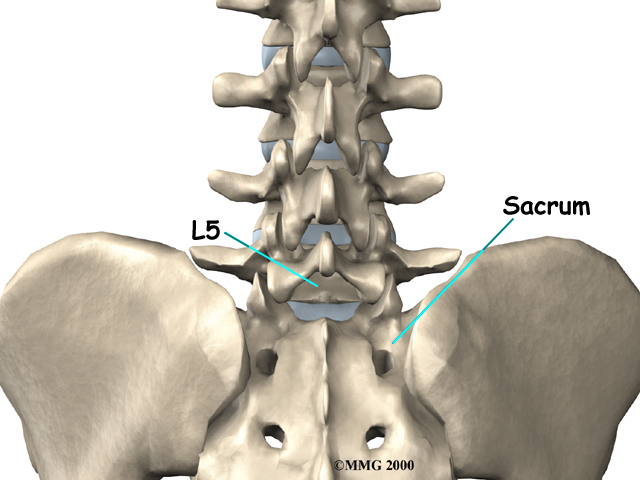

The lumbar spine is made of the lower five vertebrae. Doctors often refer to these vertebrae as L1 to L5. These five vertebrae line up to give the low back a slight inward curve. The of the lumbar spine, L5, connects to the top of the sacrum, a triangular bone at the base of the spine that fits between the two pelvic bones.

Spondylolisthesis from degeneration usually affects people over 50 years old. This condition occurs in African Americans more often than in whites. Women are affected more often than men. The effect of the female hormone estrogen on ligaments and joints is to cause laxity or looseness. The higher levels of estrogen in women may account for the greater incidence of spondylolisthesis. Degenerative spondylolisthesis mainly involves slippage of L4 over L5.

In younger patients (under 20 years old), spondylolisthesis usually involves slippage of the fifth lumbar vertebra over the top of the sacrum. There are several reasons for this. First, the connection of L5 and the sacrum forms an angle that is tilted slightly forward, mainly because the top of the sacrum slopes forward. Second, the slight inward curve of the lumbar spine creates an additional forward tilt where L5 meets the sacrum. Finally, gravity attempts to pull L5 in a forward direction.

Facet joints are small joints that connect the back of the spine together. Normally, the facet joints connecting L5 to the sacrum create a solid buttress to prevent L5 from slipping over the top of the sacrum. However, when problems exist in the disc, facet joints, or bony ring of L5, the buttress becomes ineffective. As a result, the L5 vertebra can slip forward over the top of the sacrum.

Facet joints are small joints that connect the back of the spine together. Normally, the facet joints connecting L5 to the sacrum create a solid buttress to prevent L5 from slipping over the top of the sacrum. However, when problems exist in the disc, facet joints, or bony ring of L5, the buttress becomes ineffective. As a result, the L5 vertebra can slip forward over the top of the sacrum.